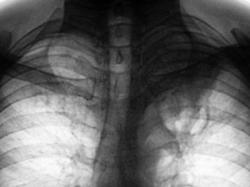

Пациент в 2007, 2008 гг. проходил профилактическую флюорографию - иллюстрации ниже. При прохождении флюорографиив 2009 г. "картинка" резко отличается от предыдущих.

2. Мужчина, 48 лет.

3. Жалобы на общую слабость. Больше жалоб никаких. В последнее время - кашель, мокрота беловатого цвета, имеются прожилки крови. Внешне - пациент недостаточного питания, анемичен, живет в семье.

По поводу личного мнения - больше склоняюсь, пока, в сторону абсцесса, однако сомнения терзают и весьма.

А разве не похоже на каверну с толстыми стенками?

Очень похоже,но при микроскопии "палки" не выявлены. Фтизиатр занимается пациентом вплотную. Уже рентгенологически обследовано "окружение" пациента, договорились с областной туб. больницей по поводу госпитализации. Но, вот полость какая-то не совсем типичная, хотя локализация и общий вид верхушки прямо указывают на "специфику".

Не должно быть туберкулёзом. Полость большая, а отсевов нет.

Как Вам версия распадающегося рака?